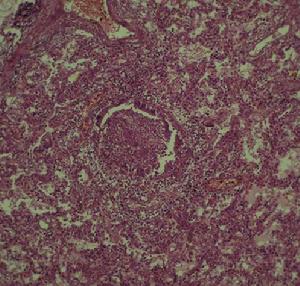

肺弓形蟲病1.病原學檢測直接光鏡檢查:血液、腦脊液、骨髓、前房水、痰、尿、唾液、其他滲液,以及淋巴結、肌組織或其他活組織等標本可採用直接塗片或印片。吉姆薩或瑞特染色,於細胞內外可見到典型新月形的弓形蟲滋養體。在組織細胞內弓形蟲亦可呈梨形或卵圓形;動物接種:標本接種於大鼠、棉鼠或金地鼠腹腔內和(或)腦內。潛伏期4天左右,動物出現不活潑、閉目、弓背、腹部膨大、呼吸窘迫症狀,解剖取肺、腹水、腦等組織作塗片染色檢查可見弓形蟲滋養體和包囊;原蟲培養:有雞胚培養和組織培養法。前者標本接種於10~12天的雞胚絨毛尿囊膜上,孵育6~7天(35℃),若陽性則尿囊膜水腫混濁,有黃白色壞死灶。2.免疫學檢查染色試驗(Sabin-Feldmandyetest):Sabin於1948年根據新鮮弓形蟲與正常血清混合後鹼性亞甲藍(美藍)染色蟲體很深,而與免疫血清混合後染色很淺或不著色,提示本試驗敏感性與特異性高。其他如間接螢光抗體、間接血凝、補體結合試驗,均具有一定的診斷參考價值;皮內試驗亦具有很高的特異性,對慢性病例有篩選作用,在流行病學調查上有診斷價值。